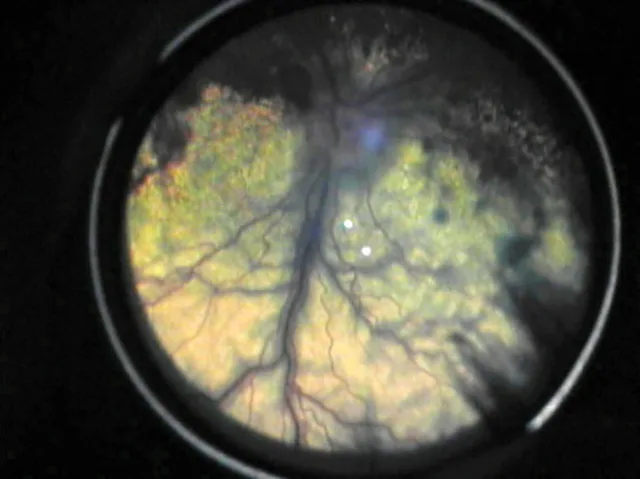

The eyes should be examined in a dark room using an indirect, direct, or PanOptic ophthalmoscope.

To examine the posterior aspect of the eye, the pupil must first be dilated using a short-acting mydriatic, such as 1% tropicamide. The eyes should be examined in a dark room using an indirect, direct, or PanOptic ophthalmoscope (WelchAllyn.com). The veterinarian should be familiar with normal posterior segment variations associated with species, coat, eye color, and age of the animal. An accurate fundic examination allows direct, noninvasive visualization of the arteries, venules, capillaries, and central nervous system.

Chorioretinitis appears clinically as a color change or loss of clarity of tissues on fundic examination. With active chorioretinitis, the addition of fluid, protein, and cells within the retina and subretinal tissues will obscure the tapetum or pigment of the choroid (hyporeflective) and may elevate or detach the retina and blur the image. Vascular involvement may result in perivascular cuffing, vasculitis, hemorrhage, and exudate (Figures 1–7). With active chorioretinitis, anterior segment involvement is common, resulting in aqueous flare, miosis, hypopyon, keratic precipitates, cataract, corneal edema, and intraocular pressure (IOP) changes. With chronicity, chorioretinitis leads to focal or diffuse retinal degeneration, tapetal hyperreflectivity, depigmentation, hyperpigmentation, and vascular attenuation (Figures 8–11).